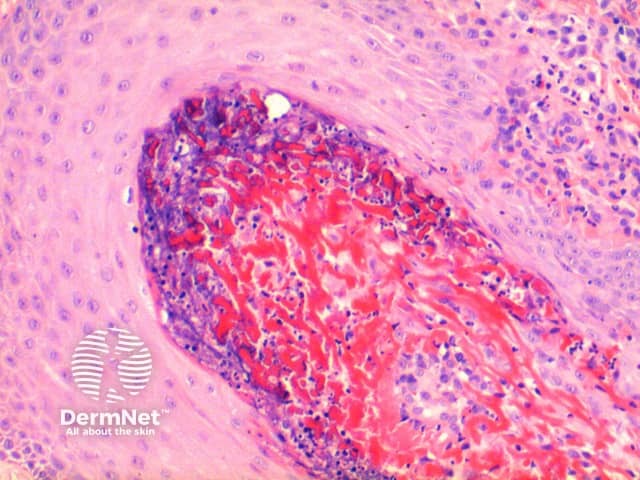

Low power of histology of elastosis perforans serpiginosa demonstrates a column of keratotic debris forming a focal invagination through a hyperplastic epidermis (figure 1). Closer inspection identifies material undergoing transepidermal elimination (figure 2). Brightly eosinophilic fibres are seen within the extruded material, mixed with keratinous debris and a mixed inflammatory cell infiltrate (figures 3, 4).

Figure 4